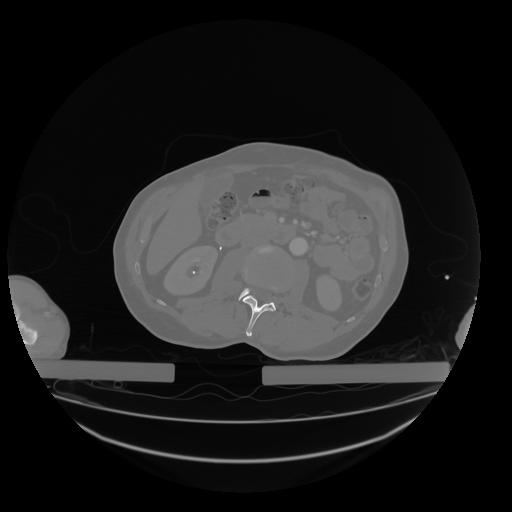

28 CUERPO,CE,Vol,2.0,CUERPO,,